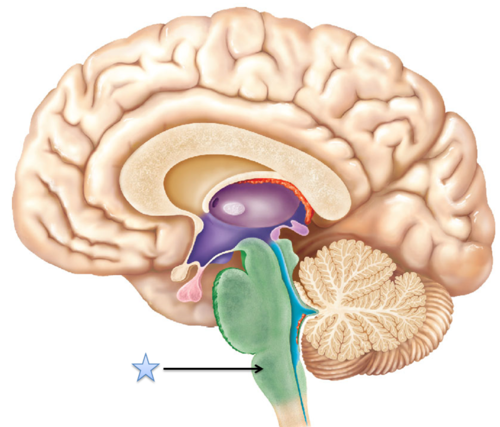

reticular formation

a nerve

network that travels through the

brainstem and thalamus and plays

an important role in controlling

arousal.

network that travels through the

brainstem and thalamus and plays

an important role in controlling

arousal.

22

New cards

reticular formation (pic)